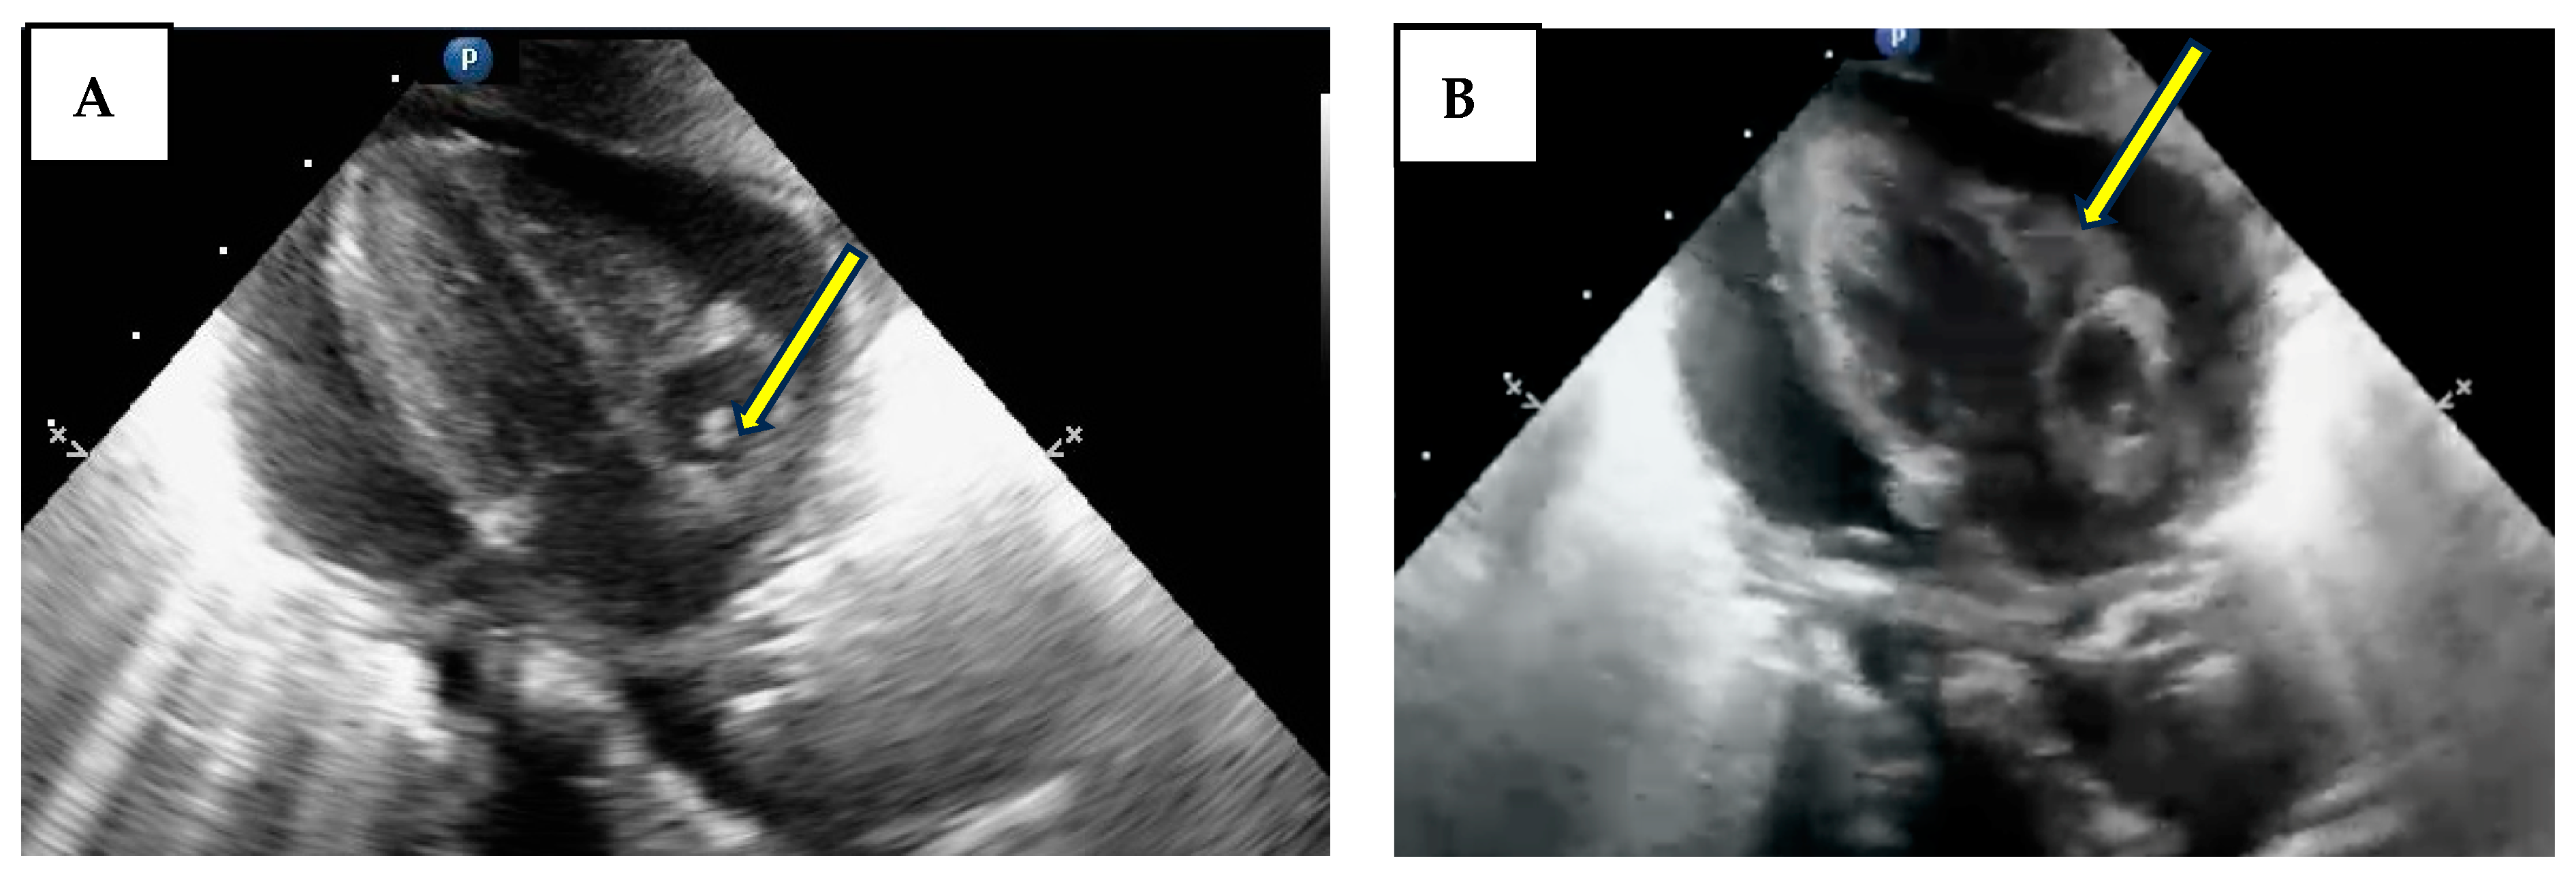

Radiological re-evaluation of the catheters is not done routinely in our unit, but cardiac POCUS is frequently performed, and the absence of pleural or pericardial effusion is always verified. Figure 2 shows a variety of positions of the tip.

Figure 2. Picture (A,B)—tip placement accepted for a CVC inserted on the femoral vein (T11–T10, S1) (arrow). Picture (C)—CVC inserted in the upper body causing PEff due to very deep insertion (T9–T10) (arrow). Picture (D)—normal position of a CVC inserted in the upper body (T4) (arrow).

Figure 4. Pericardial effusion and tamponade. Picture (A) subcostal view-long axis-4 chambers view showing the CVC inside the right atrium (arrow). Picture (B) subcostal view-long axis-4 chambers view showing the diastolic collapse of the right ventricle (arrow).